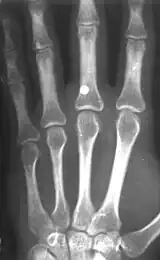

BB gun injury showing a 4.5 mm steel BB that penetrated the middle finger on the left hand

BB guns can shoot faster than 60 m/s (200 ft/s), but are often less powerful than a conventional pellet airgun. Pellet airguns have the ability to fire considerably faster, even beyond 170 m/s (560 ft/s).[4][5][6] Although claims are often exaggerated, a few airguns can actually fire a standard 0.177 caliber lead pellet faster than 320 m/s (1,000 ft/s), but these are generally not BB-firing guns.

A BB with a velocity of only 45 m/s (150 ft/s) has skin-piercing capability, and a velocity reaching 60 m/s (200 ft/s) can fracture bone.[7] This is potentially lethal, and this potential increases with velocity, but also rapidly decreases with distance. The effective penetrating range of a BB gun with a muzzle velocity of 120 to 180 m/s (390 to 590 ft/s) is approximately 18 m (60 ft). A person wearing jeans at this distance would not sustain serious injury. However, even at this distance a BB still might penetrate bare skin, and even if not, could leave a severe and painful bruise. The maximum range of a BB gun in the 120 to 180 m/s (390 to 590 ft/s) range is 100–200 metres approximately,[8] provided the muzzle is elevated to the optimum angle.